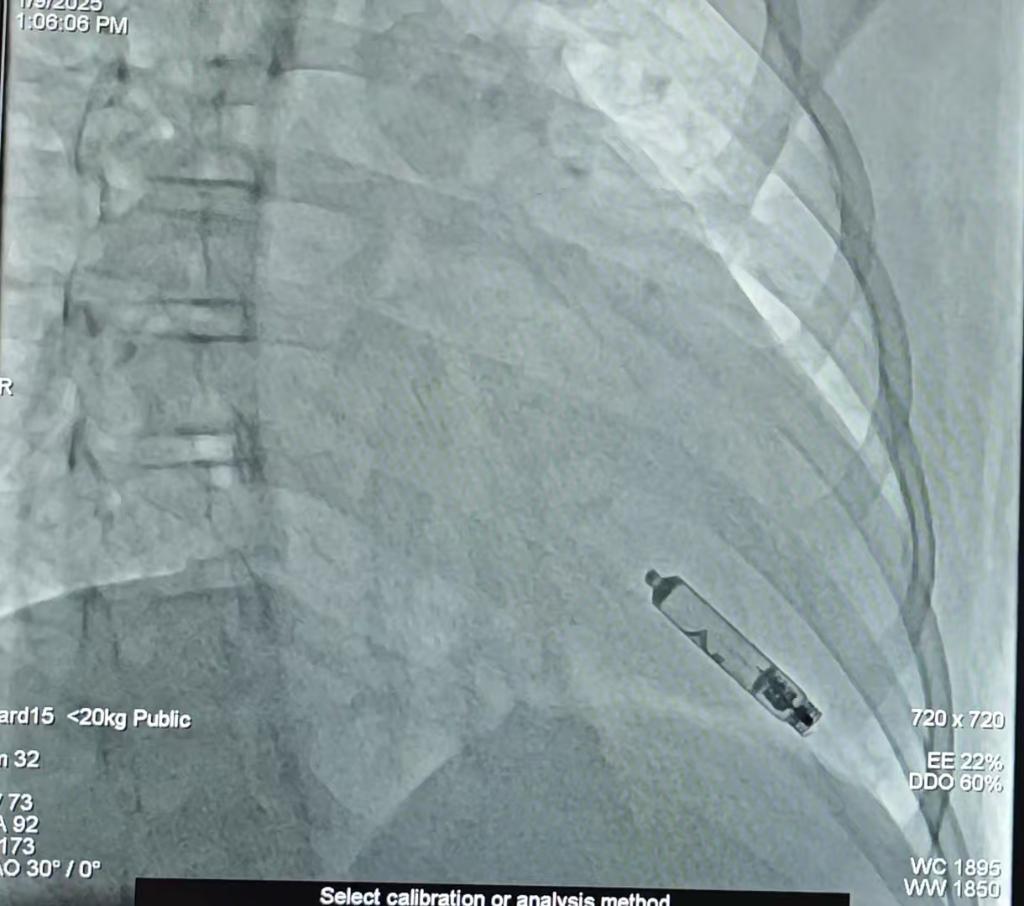

图为无导线可回收心脏起搏器植入后影像图。重庆医科大学附属儿童医院供图

据了解,该新型起搏器长度仅3.8厘米,直径6.5mm,重量仅2g,通过头端1.63mm的螺旋电极旋入心肌发挥起搏作用,为儿童患者缓慢性心律失常的起搏治疗带来了更大的益处。与传统起搏器相比,其优点在于仅通过微创方式经股静脉将起搏器植入右心室,无需切开皮肤及导线;此外,该起搏器电池耗尽后亦可通过微创方式回收,使用寿命为17到20年。

今年1月9日,吕铁伟带领心血管科心律失常医护团队,经过一系列精细操作,将起搏器的输送系统置于右心室,然后将起搏器置于右心室间隔靠心尖处心肌内。“经过数次测试,起搏器的各项参数良好,起搏器成功植入患儿体内。术后,患儿的心率迅速恢复正常,各项生命体征平稳、恢复良好。”吕铁伟说。